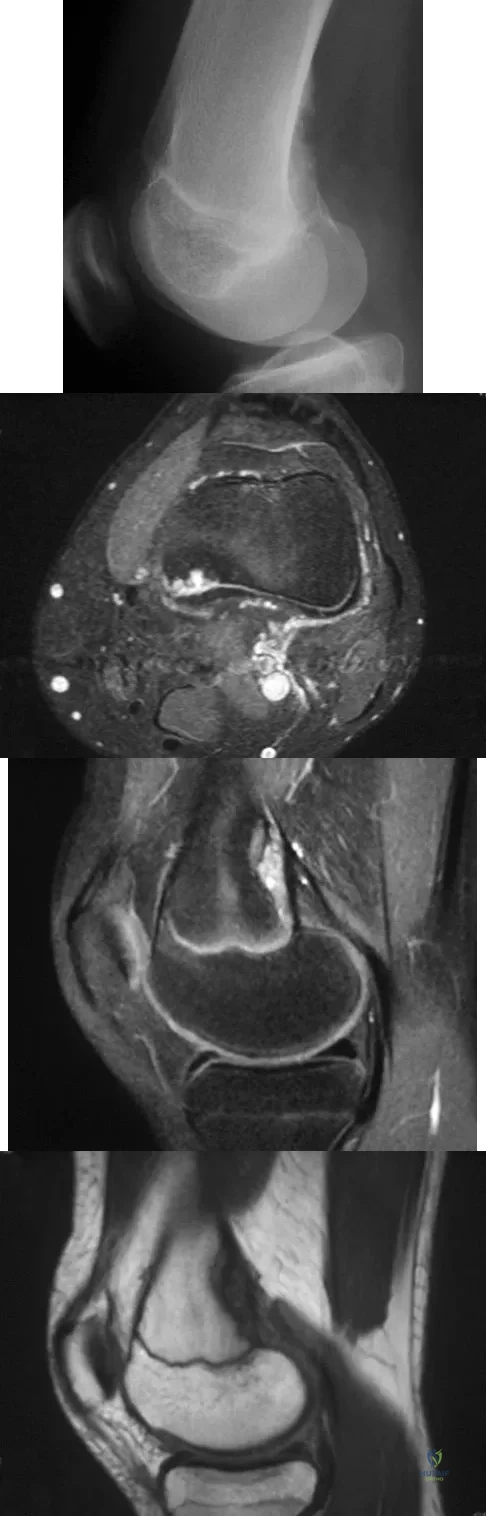

A 14-year-old girl reports bilateral patellofemoral symptoms. Based on the radiograph and MRI scans shown in Figures 23a through 23d, what is the next most appropriate step in management of the lesion?

A 13-year-old boy has knee pain after sustaining a mild twisting injury while playing basketball 4 weeks ago. Radiographs and MRI scans are shown in Figures 24a through 24d, and biopsy specimens are shown in Figures 24e and 24f. Treatment should consist of